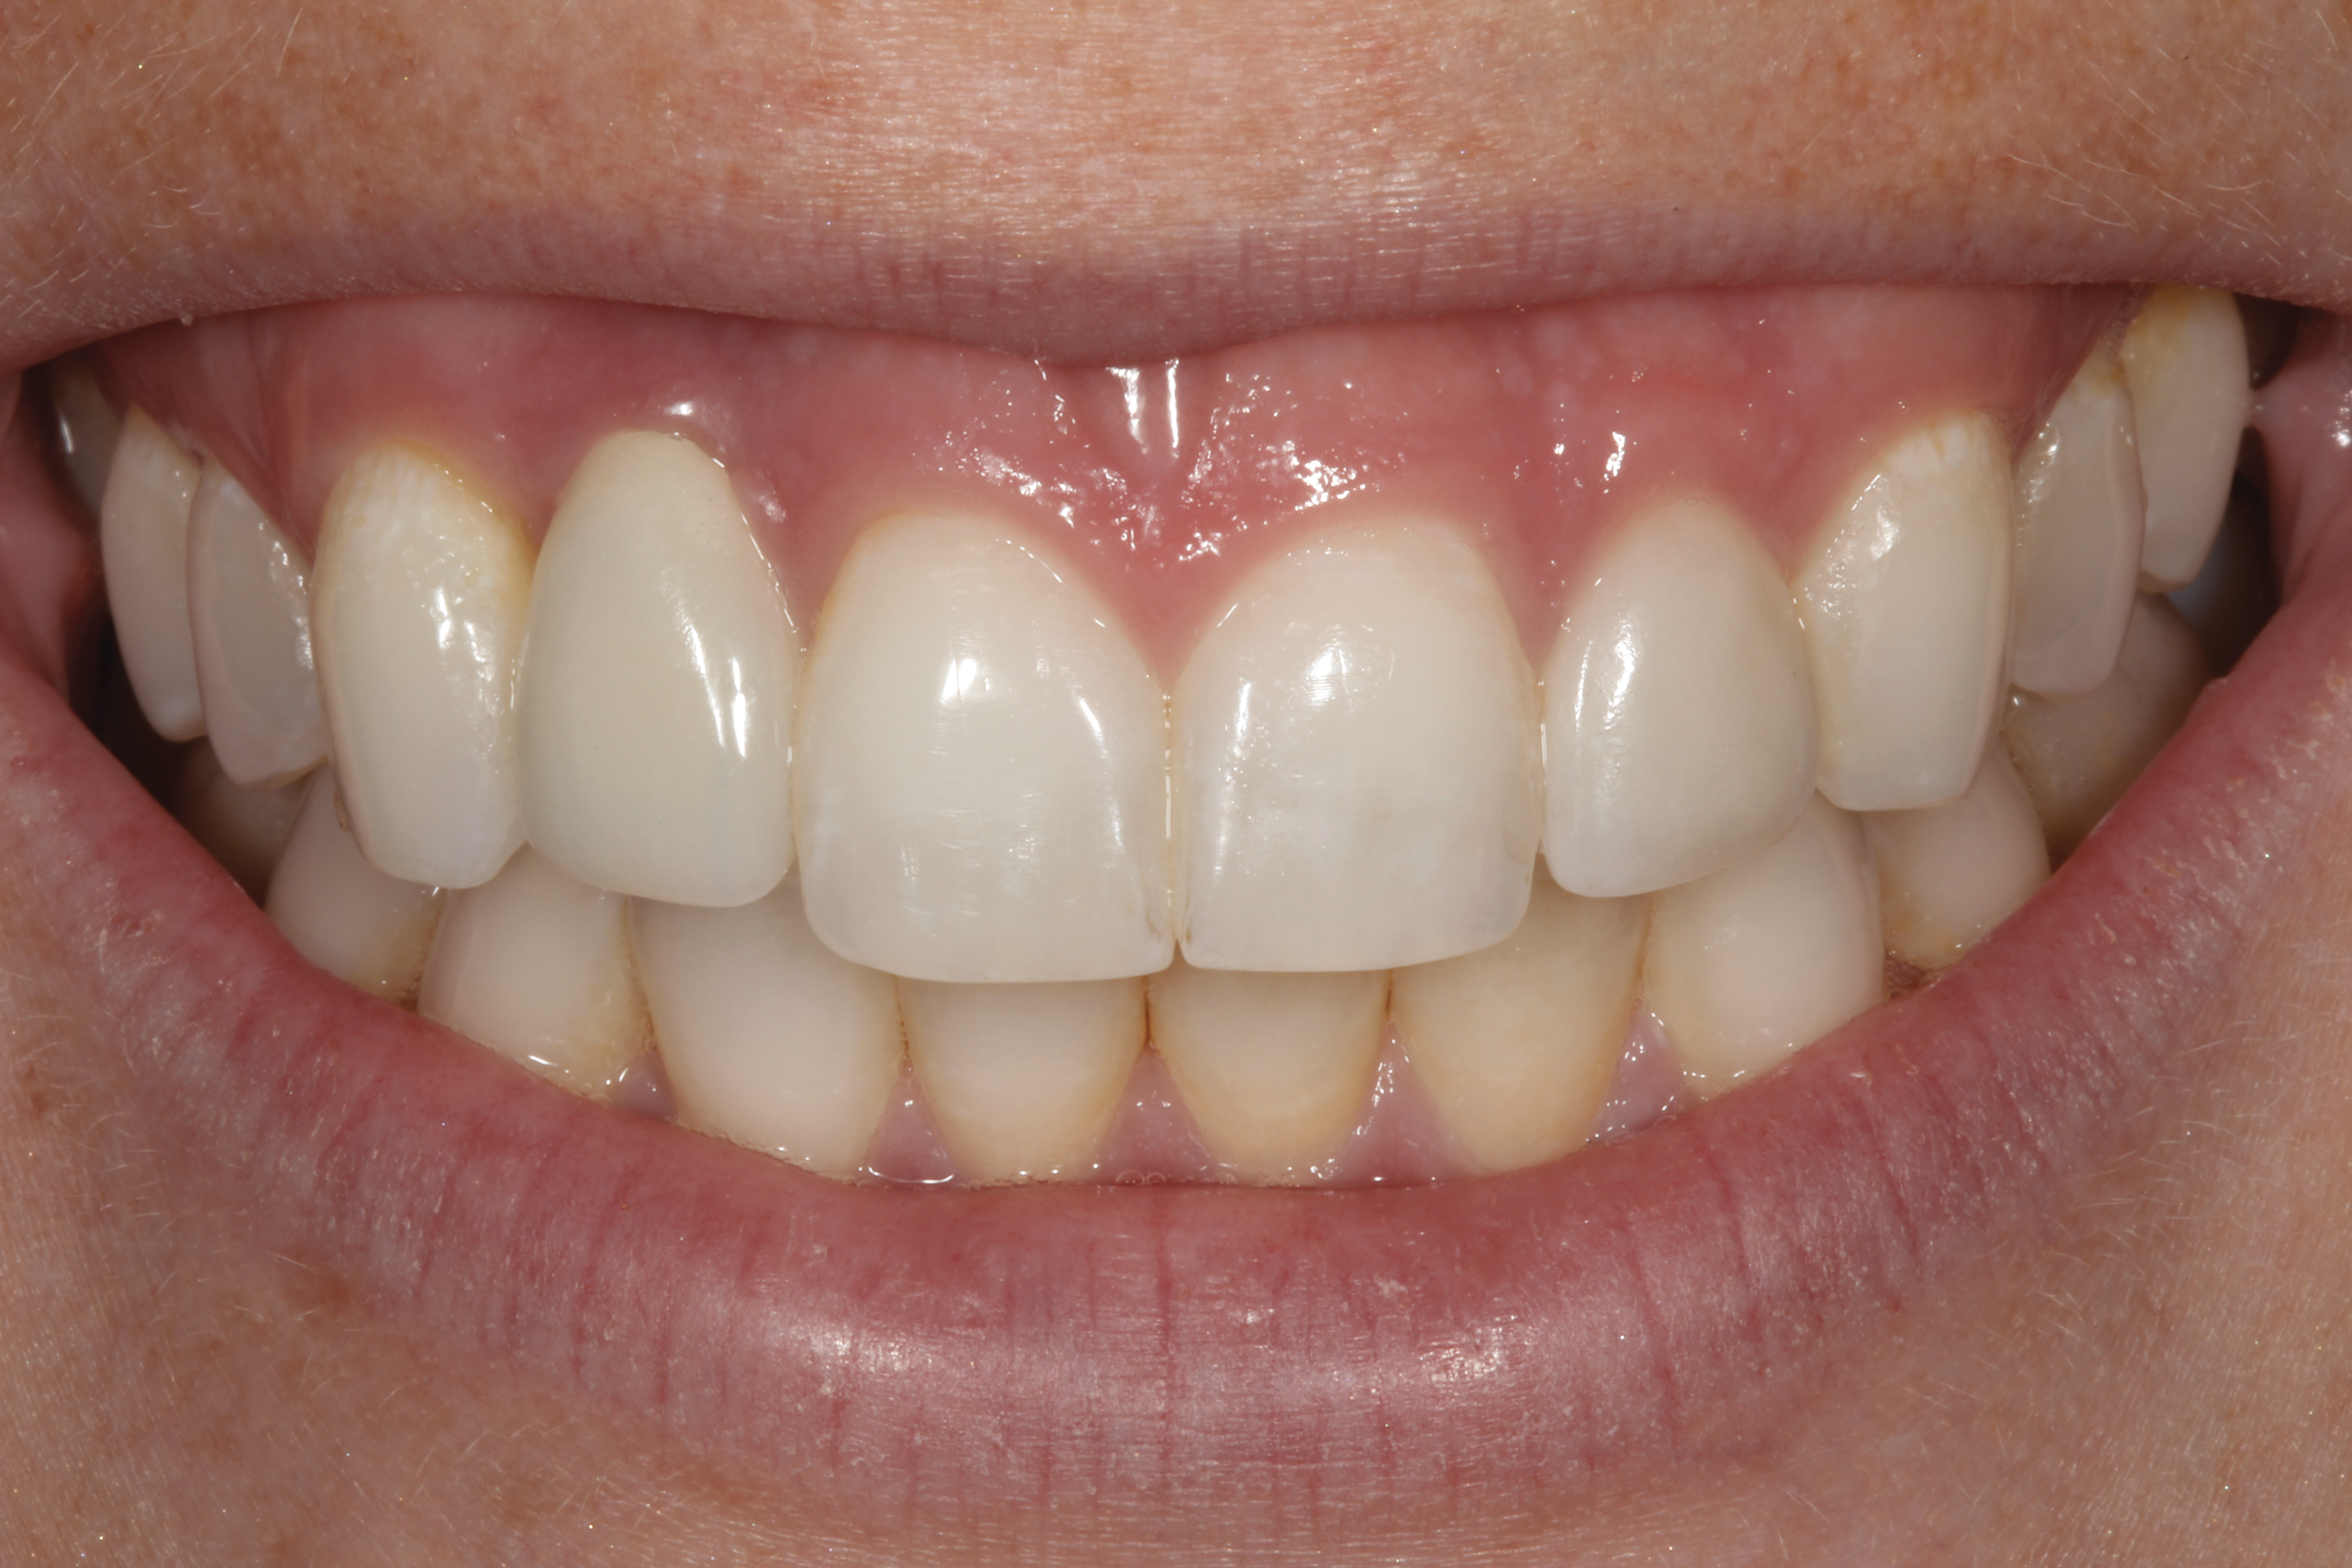

Fig 14. The extraoral smile view of the esthetically satisfied patient at 4 years recall.

Figure 14